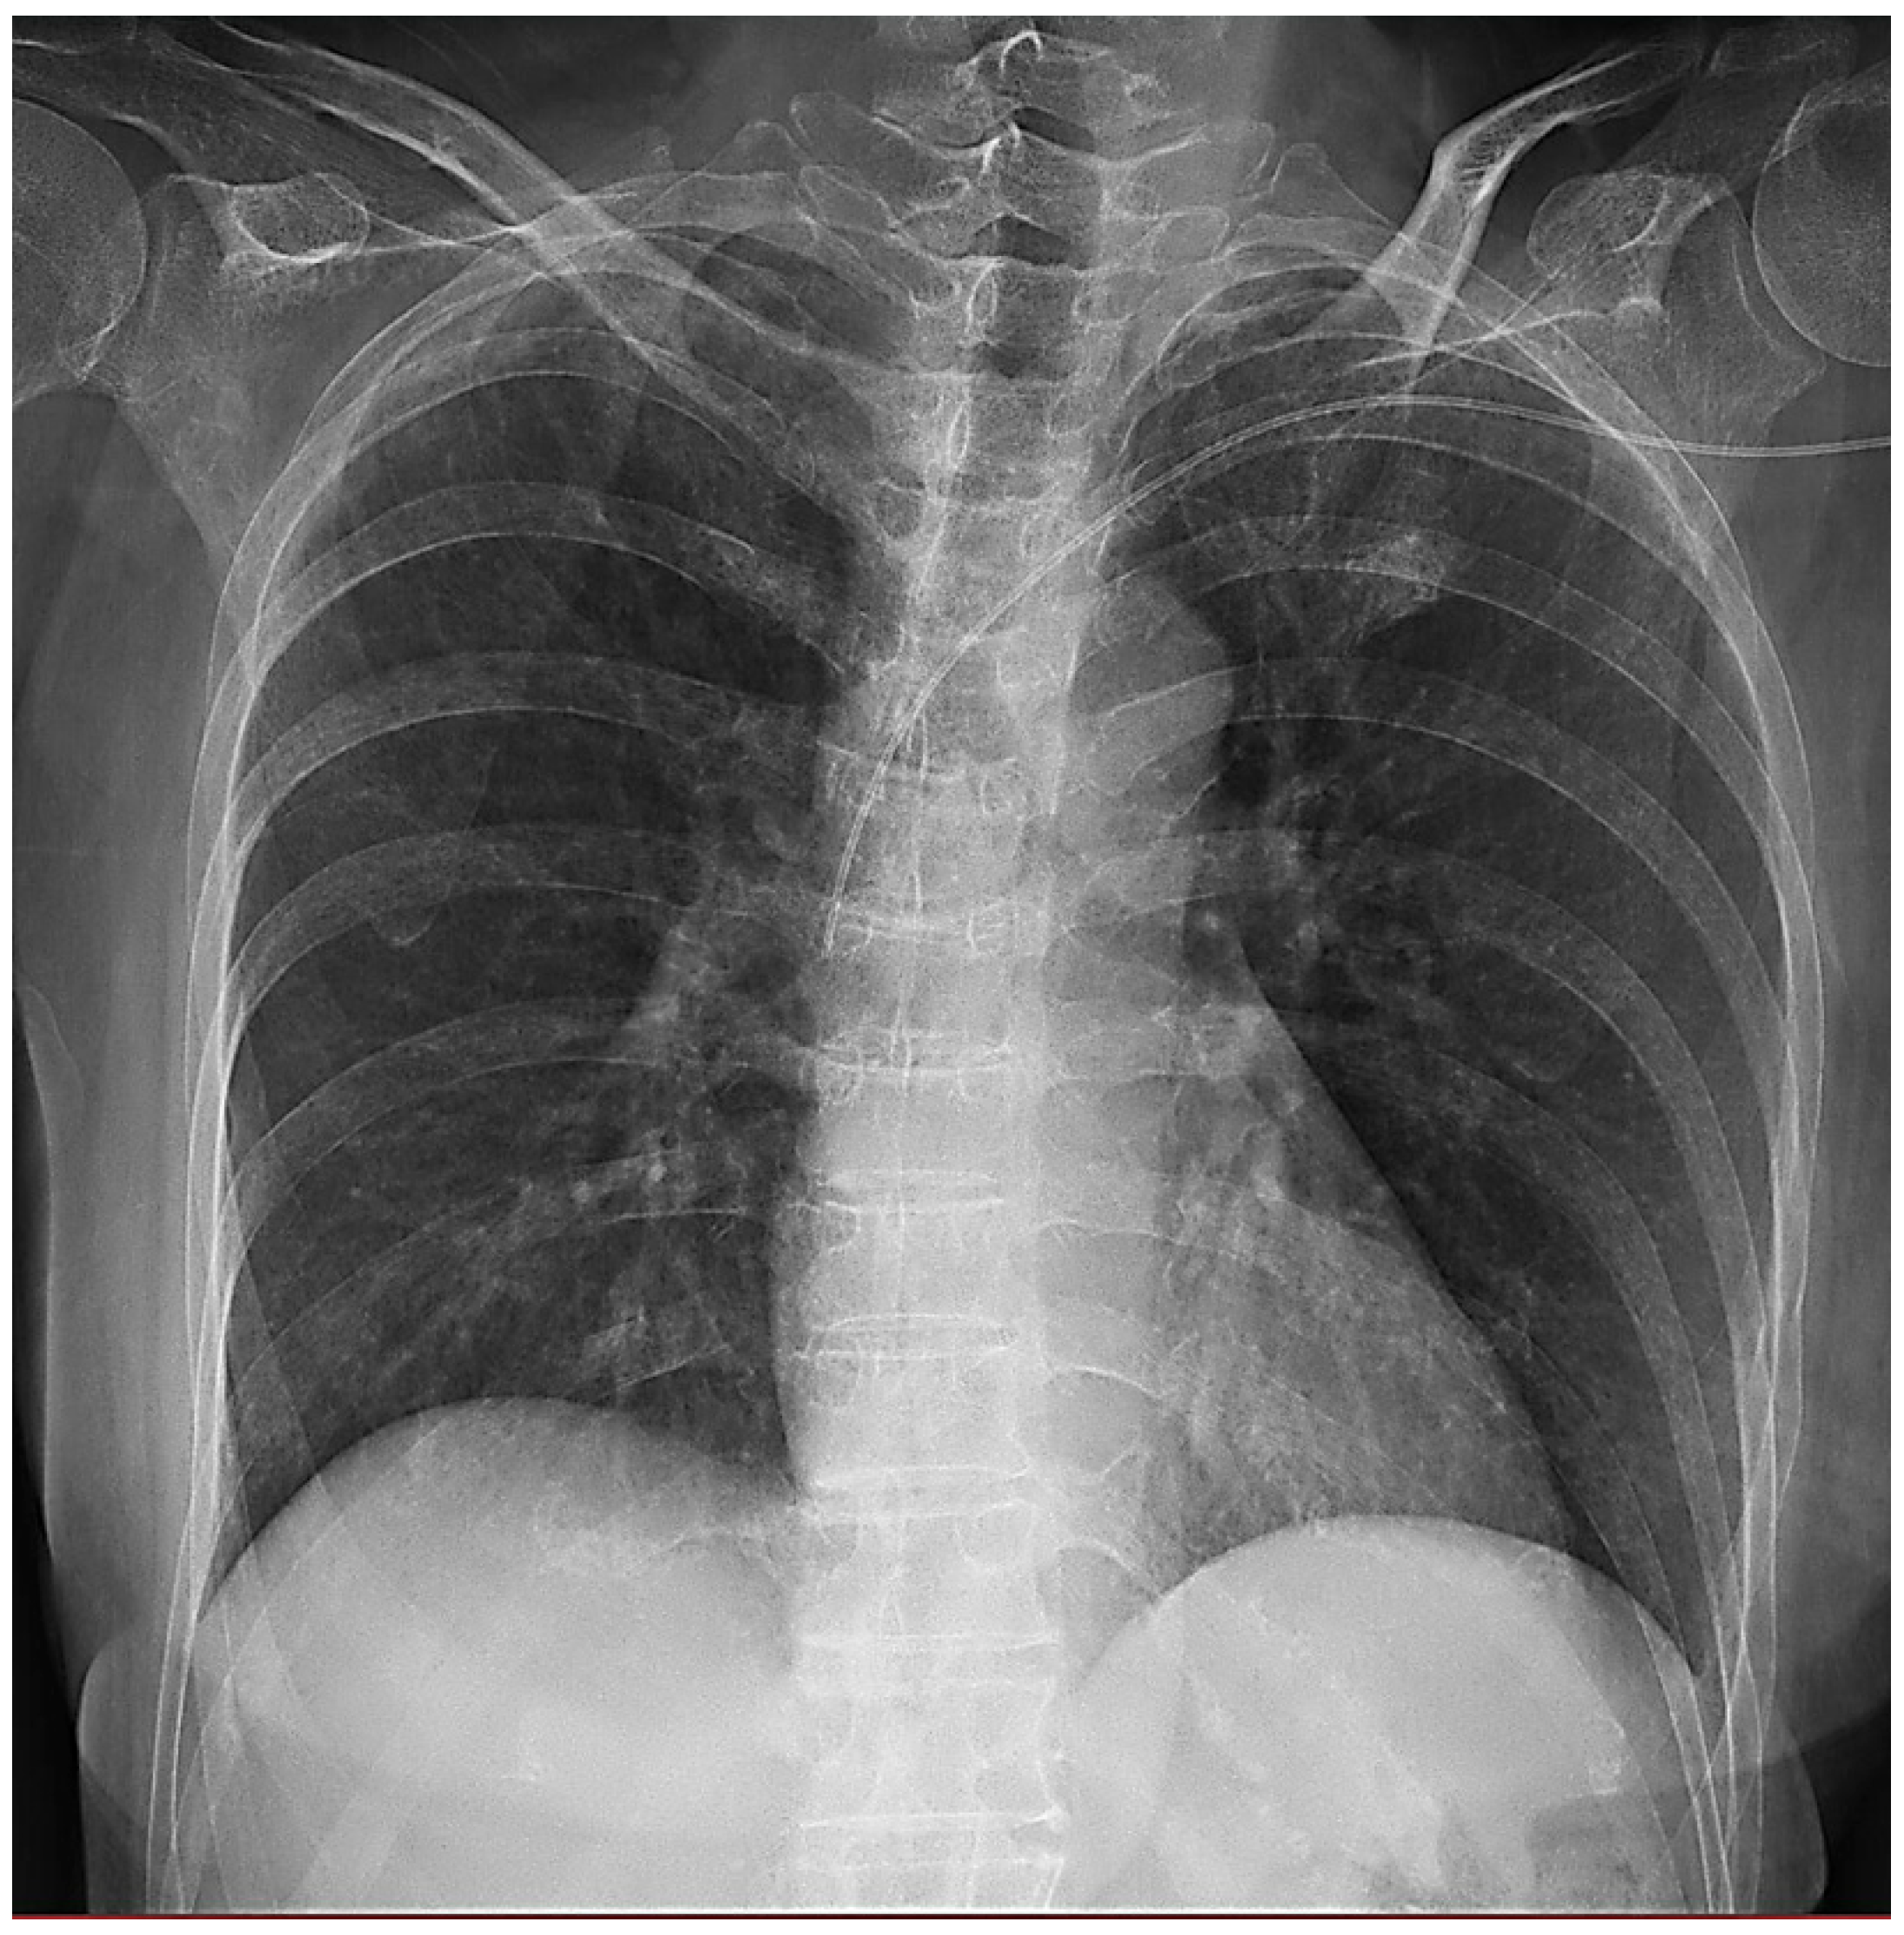

Abstract

2. Materials and Methods

2.1. Study Design and Patioents

2.2. X-Ray System and Imaging Protocol